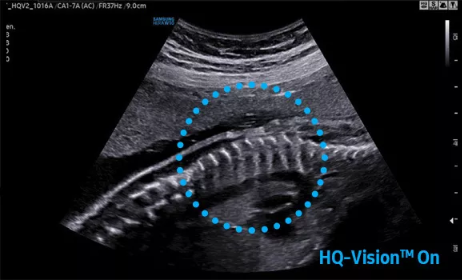

Hera i 10繼承并升級(jí)了全球首款5D超聲“三星麥迪遜WS80A”的“晶體結(jié)構(gòu)”成像理念,即將CrystalBeam?波束形成技術(shù)、CrystalLive?超聲成像引擎、S-Vue Transducer?視覺傳感器集于一身,提供更清晰的圖像。

CrystalBeam?是一種新的波束形成技術(shù),利用任意波形傳輸、大規(guī)模并行波束形成和合成孔徑技術(shù),產(chǎn)生更快的幀速率和更好的圖像均勻性。

2D成像方面,Hera i10集成了包括ShadowHDR?、HQ-Vision?、ClearVision等多項(xiàng)具有三星“血統(tǒng)”的技術(shù),加強(qiáng)了圖像的陰影抑制、減少偽影、緩和模糊區(qū)。